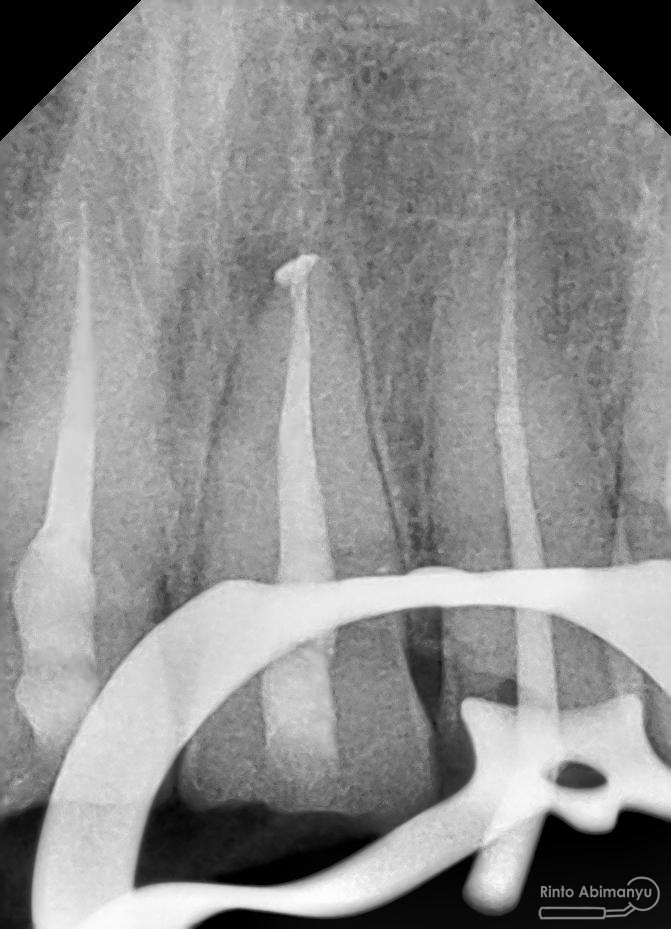

Kemudian dilakukan pengepasan guttap dan difoto ronsen….

Foto radiografis trial guttap

Dari ronsen terlihat guttap sudah pas dan langsung hari itu juga saya lakukan pengisian saluran akar kemudia pasien pulang…. Pada saat selesai pengisian tidak saya lakukan ronsen lagi karena saya merencanakan ronsen evaluasi pengisiannya sekalian foto ronsen saat pengepasan guttap pada gigi 22 saja biar efektif…